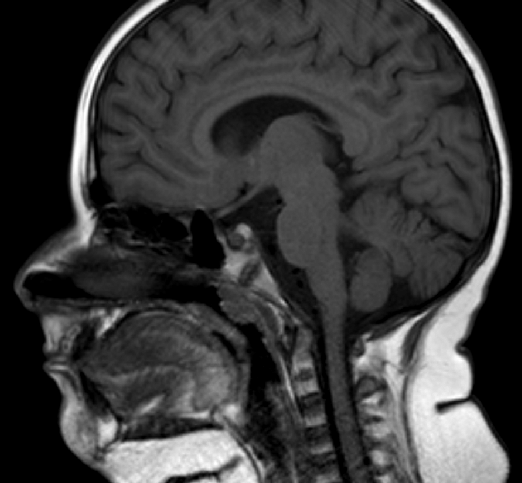

Various practices are performed; while diagnosing the presence of a Tornwaldt cyst. Those practices involve a CT scan and MRI predominantly.

On a CT scan, the cyst or lesions appear low density and well-circumscribed and are usually non-enhancing. However, there is a probability of richness of the fluid protein; if that is the case, then it may even show resemblance to a solid lesion and may be hyper-attenuating.

The results obtained from an MRI usually indicate the existence of cysts as being well-circumscribed with a narrow wall. The T1 signal is variable depending upon the present protein content, the T2 signal is high, and no enhancement is generally visible.

To diagnose such a cyst, a doctor inserts a viewing tube through the passage of the nose. That tube is known as a nasopharyngoscope. Afterward, the diagnosis is confirmed with imaging tests such as a CT scan or an MRI.